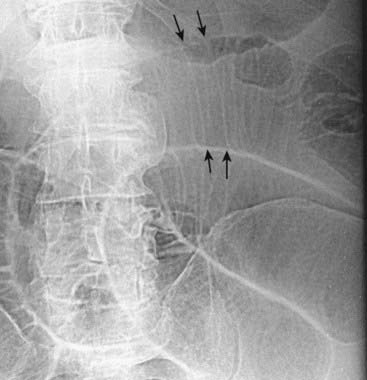

Figure 13-3 Normal colonic distension.

The colon can normally distend to the size of the diameter of the colon as seen on a barium enema (solid white arrows). Beyond this size, the colon would be considered dilated. This patient has had a double-contrast barium enema examination in which both air and barium are instilled as contrast agents. The combination allows for excellent visualization of the mucosal surface of the colon.